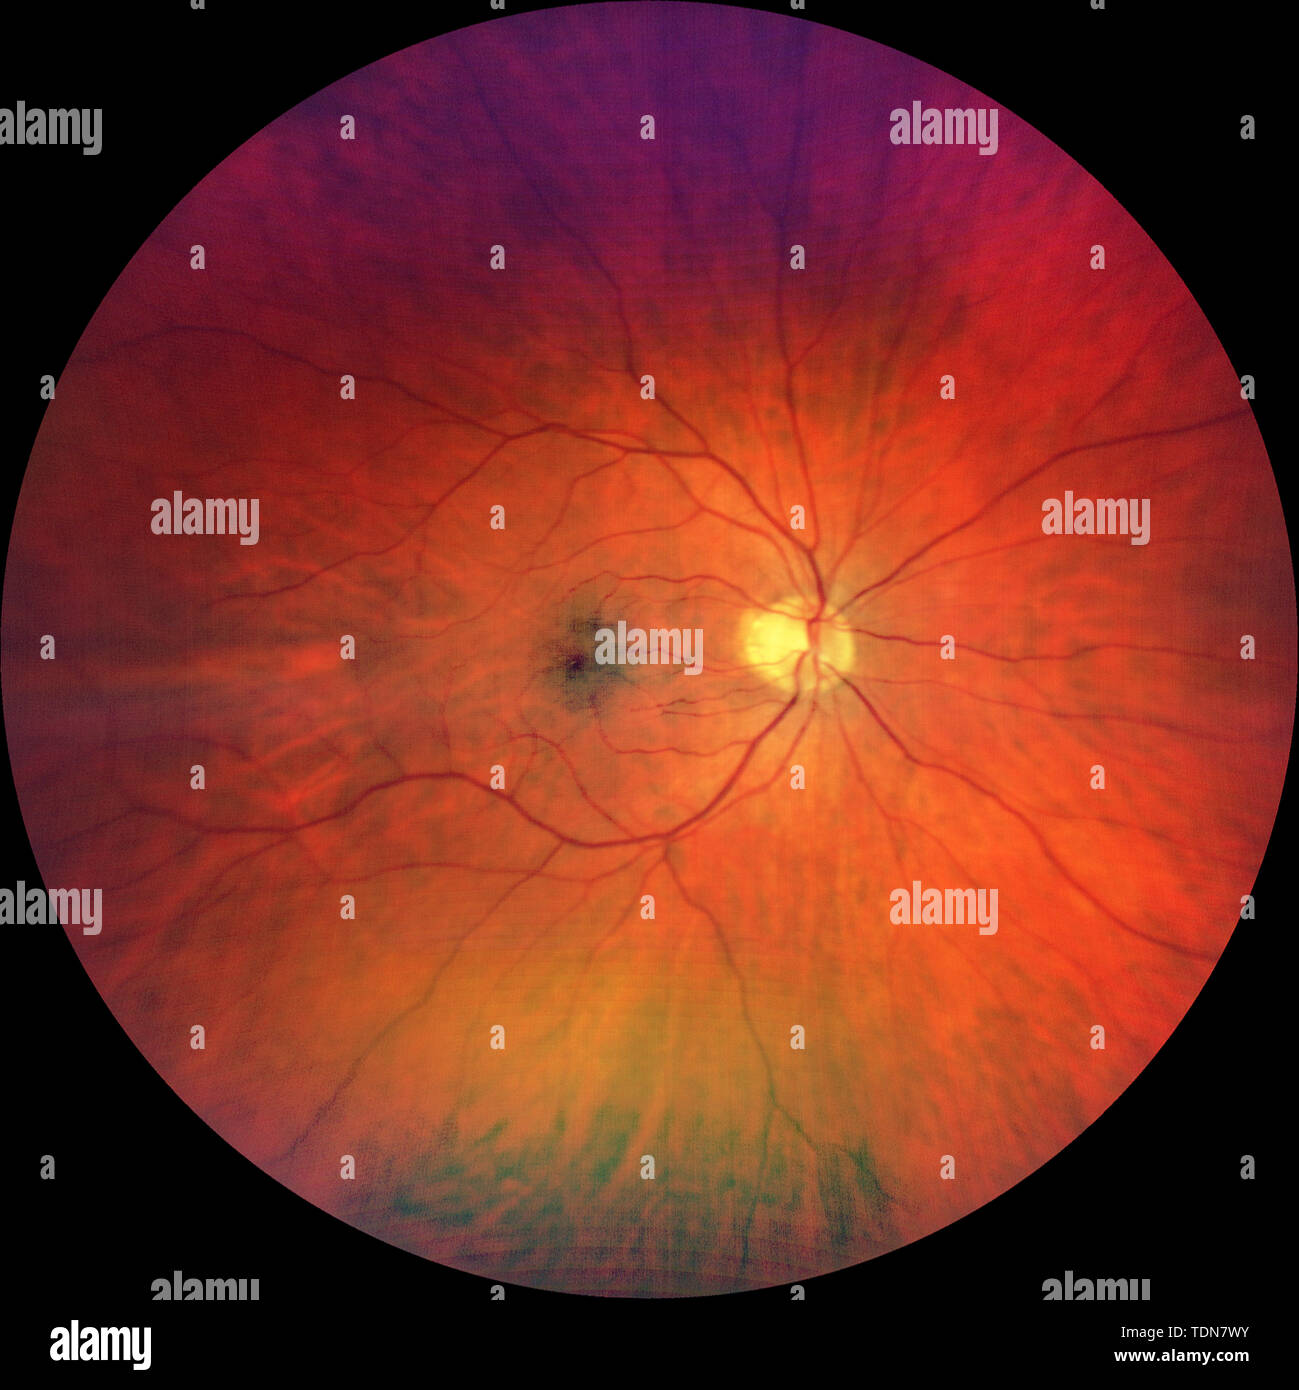

Photograph of the Fundus Oculi: left and right eye Stock Photohttps://www.alamy.com/image-license-details/?v=1https://www.alamy.com/photograph-of-the-fundus-oculi-left-and-right-eye-image249402864.html

Photograph of the Fundus Oculi: left and right eye Stock Photohttps://www.alamy.com/image-license-details/?v=1https://www.alamy.com/photograph-of-the-fundus-oculi-left-and-right-eye-image249402864.htmlRMTDN7W4–Photograph of the Fundus Oculi: left and right eye

Photograph of the Fundus Oculi: left eye Stock Photohttps://www.alamy.com/image-license-details/?v=1https://www.alamy.com/photograph-of-the-fundus-oculi-left-eye-image249402865.html

Photograph of the Fundus Oculi: left eye Stock Photohttps://www.alamy.com/image-license-details/?v=1https://www.alamy.com/photograph-of-the-fundus-oculi-left-eye-image249402865.htmlRMTDN7W5–Photograph of the Fundus Oculi: left eye

Photograph of the Fundus Oculi: right eye Stock Photohttps://www.alamy.com/image-license-details/?v=1https://www.alamy.com/photograph-of-the-fundus-oculi-right-eye-image249402887.html

Photograph of the Fundus Oculi: right eye Stock Photohttps://www.alamy.com/image-license-details/?v=1https://www.alamy.com/photograph-of-the-fundus-oculi-right-eye-image249402887.htmlRMTDN7WY–Photograph of the Fundus Oculi: right eye